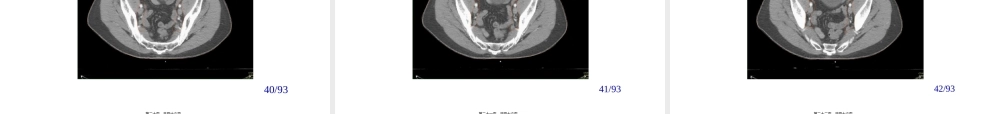

PelvicNodalConsensusCTVContours:HighRisk/LocallyAdvancedAdenocarcinomaoftheProstateColleenAFLawtonMDMedicalCollegeofWisconsin第一页,共四十六页。BasedonDataPresentedConsensusWasObtainedIncluding:•TreatmentofPresacralLNs(subaorticonly)•主动脉弓下骶前淋巴结的治疗•7mmaroundiliacvessels,carvingoutbowel,bladderandbone•髂血管周围7mm,勾画肠道、膀胱、骨骼•CommencecontouringatdistalcommoniliacvesselsatL5/S1interspace•从L5/S1间隙髂总血管远端开始•Stopexternaliliaccontoursattopoffemoralheads(boneylandmarkforIng.ligament)•髂外勾画至股骨头顶端〔Ing.ligament的骨性标志〕•StopcontoursofobturatorLNsattopofsymphsispubis•闭孔淋巴结勾画至耻骨联合第二页,共四十六页。2323/93第三页,共四十六页。2424/93第四页,共四十六页。2525/93第五页,共四十六页。2626/93第六页,共四十六页。2727/93第七页,共四十六页。2828/93第八页,共四十六页。2929/93第九页,共四十六页。3030/93第十页,共四十六页。3131/93第十一页,共四十六页。3232/93第十二页,共四十六页。3333/93第十三页,共四十六页。3434/93第十四页,共四十六页。3535/93第十五页,共四十六页。3636/93第十六页,共四十六页。3737/93第十七页,共四十六页。3838/93第十八页,共四十六页。3939/93第十九页,共四十六页。4040/93第二十页,共四十六页。4141/93第二十一页,共四十六页。4242/93第二十二页,共四十六页。4343/93第二十三页,共四十六页。4444/93第二十四页,共四十六页。4545/93第二十五页,共四十六页。4646/93第二十六页,共四十六页。4747/93第二十七页,共四十六页。4848/93第二十八页,共四十六页。4949/93第二十九页,共四十六页。5050/93第三十页,共四十六页。5151/93第三十一页,共四十六页。5252/93第三十二页,共四十六页。5353/93第三十三页,共四十六页。5454/93第三十四页,共四十六页。5555/93第三十五页,共四十六页。5656/93第三十六页,共四十六页。5757/93第三十七页,共四十六页。5858/93第三十八页,共四十六页。5959/93第三十九页,共四十六页。6060/93第四十页,共四十六页。6161/93第四十一页,共四十六页。6262/93第四十二页,共四十六页。6363/93第四十三页,共四十六页。6464/93第四十四页,共四十六页。65第四十五页,共四十六页。内容总结PelvicNodalConsensusCTVContours:HighRisk/LocallyAdvancedAdenocarcinomaoftheProstateColleenAFLawtonMDMedicalCollegeofWisconsin。TreatmentofPresacralLNs(subaorticonly)。65第四十六页,共四十六页。